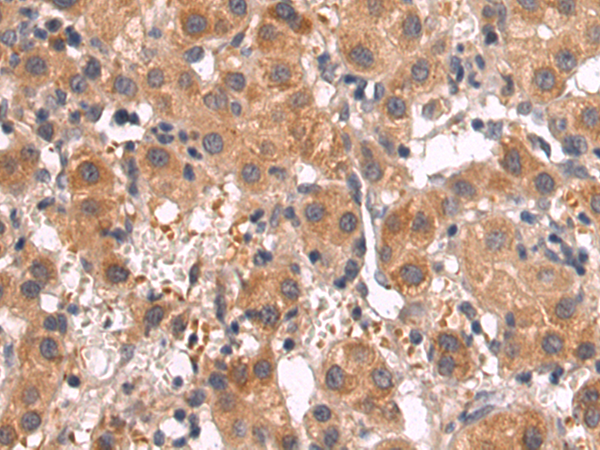

IHC positive control: |

Human tonsil |

IHC Recommend dilution: |

25-100 |